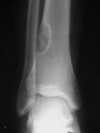

Cullens sign

Peri-umbilical ecchymosis

Acute pancreatitis